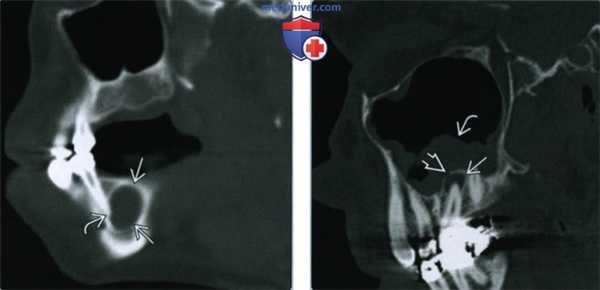

(Слева) На панорамной реформатированной КЛКТ определяется разрежение костной ткани возле периодонта зуба, подвергнутою эндодонтическому лечению, а также расширение периапикальною пространства ПДС с наличием широкой зоны склероза вокруг участка разрежения.

(Справа) На периапикальной рентгенограмме определяется склерозирующий остеит вокруг верхушечной и средней трети корней первого моляра нижней челюсти слева. В области фуркации определяется разрежение структуры костной ткани возле периодонта с выходом заполнителя вследствие перфорации мезиальною корня при неудачной попытке эндодонтическою лечения.

(Справа) На периапикальной рентгенограмме определяется склерозирующий остеит вокруг верхушечной и средней трети корней первого моляра нижней челюсти слева. В области фуркации определяется разрежение структуры костной ткани возле периодонта с выходом заполнителя вследствие перфорации мезиальною корня при неудачной попытке эндодонтическою лечения. (Слева) На профильном срезе (КЛКТ) визуализируется трансплантат, закрывающий дефект после удаления зуба. Некроз пульпы стал причиной выраженною склерозирующею остеита вокруг зуба. Склероз сохраняется даже после удаления зуба, достигая кортикальных пластинок нижней челюсти и распространяясь в канал НАН.

(Справа) На панорамной реформатированной КЛКТ определяется легкий периапикальный склероз вокруг расширенного пространства ПДС у вершины корня зуба. СО стороны зубов, подвергшихся эндодонтическому лечению, не должны обнаруживаться признаки воспаления до реставрации коронок.